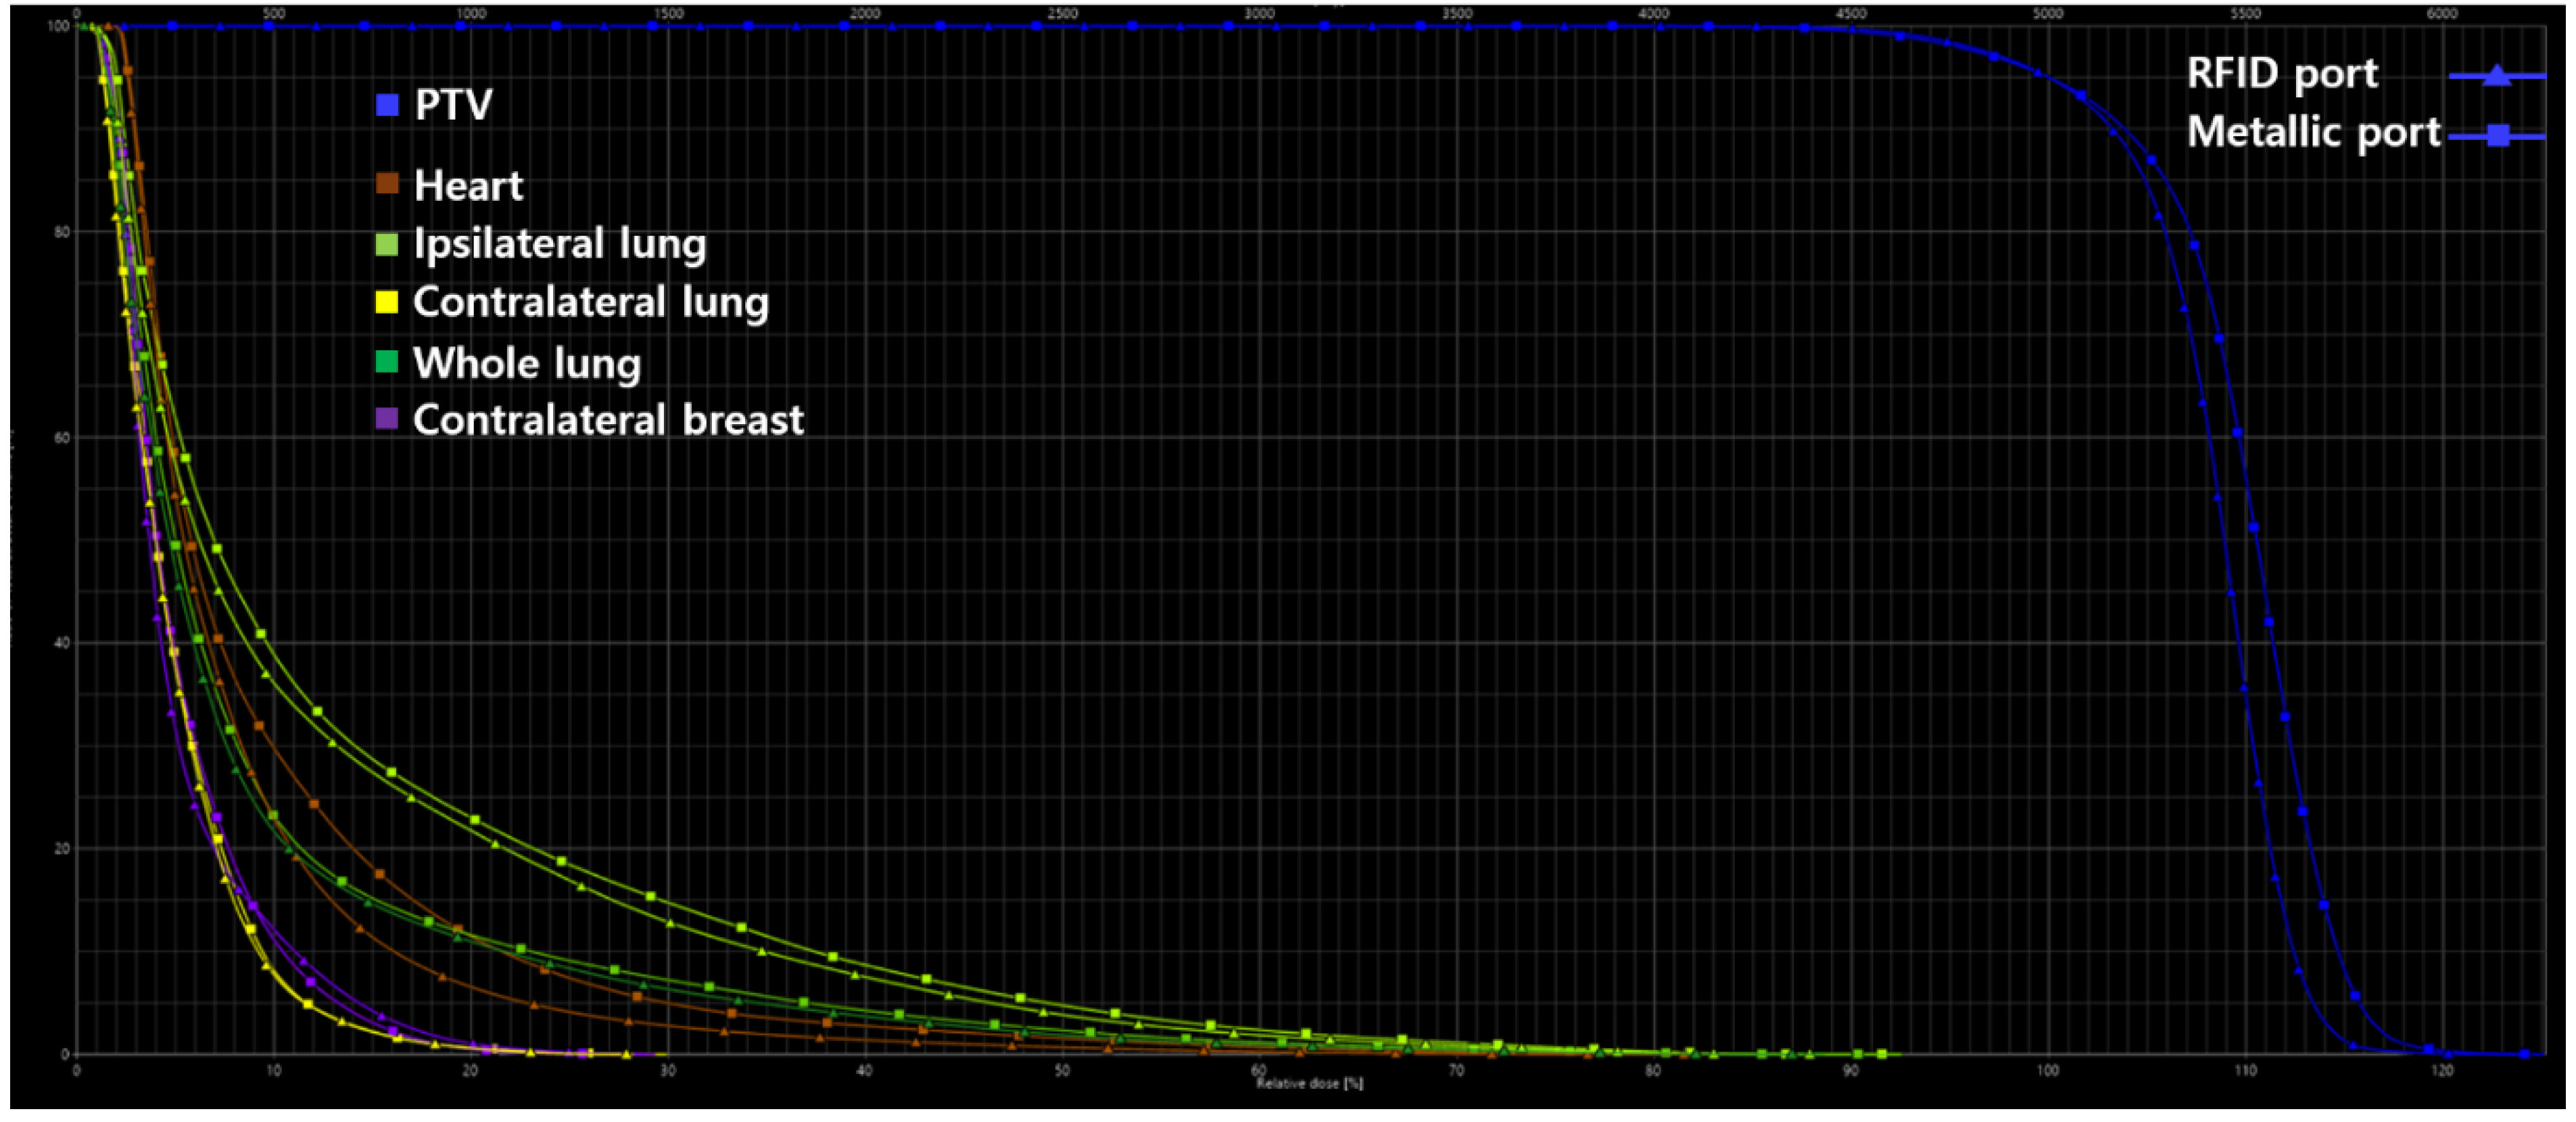

2.5. Assessment of Plan Quality

| Parameter | RFID Port | Metallic Port | Percentage Difference |

|---|---|---|---|

| PTV | |||

| HI | 1.31 | 1.32 | 0.76 |

| CI | 0.95 | 0.95 | 0 |

| QOC | 0.92 | 0.90 | 2.19 |

| V95, % | 98.40 | 98.10 | 0.30 |

| V107, % | 71.70 | 80.80 | 11.93 |

| Heart | |||

| V5Gy, % | 22.91 | 29.75 | 25.97 |

| V10Gy, % | 6.54 | 11.46 | 54.66 |

| V15Gy, % | 2.77 | 4.97 | 56.84 |

| V20Gy, % | 1.39 | 2.75 | 65.70 |

| V30Gy, % | 0.23 | 0.68 | 98.90 |

| Dmean, Gy | 4.08 | 4.92 | 18.66 |

| Ipsilateral lung | |||

| V5Gy, % | 36.08 | 38.86 | 7.41 |

| V15Gy, % | 12.85 | 14.73 | 13.63 |

| V20Gy, % | 7.50 | 8.67 | 14.47 |

| V30Gy, % | 1.87 | 2.36 | 23.16 |

| Dmean, Gy | 6.43 | 6.94 | 7.62 |

| Contralateral lung | |||

| Dmean, Gy | 2.44 | 2.51 | 2.82 |

| Whole lung | |||

| V20Gy, % | 3.69 | 4.25 | 14.10 |

| Dmean, Gy | 4.40 | 4.68 | 6.16 |

| Contralateral breast | |||

| Dmean, Gy | 2.58 | 2.68 | 3.80 |